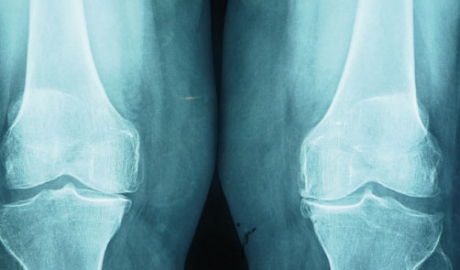

Lo más habitual en nuestra cirugía es la utilización de células mesenquimales (CM) procedentes de la médula ósea que mediante diferentes mecanismos pueden concentrarse o incluso expandirse y orientarse hacia tejidos concretos. La falta de experiencia clínica suficiente nos hace recomendarlas sólo en casos muy concretos: La falta de consolidación ósea (pseudoartrosis), necrosis óseas de cadera (cabeza del fémur) o necrosis ósea de la rodilla (cóndilo femoral). También se esta utilizando en casos de lesiones focales de cartílago y algunos autores recomiendan su indicación en la artrosis.

- En artrosis, en las que el paciente no es sensible a tratamientos convencionales

- Condropatias y osteocondritis

- Lesiones de ligamentos de la rodilla u otras articulaciones